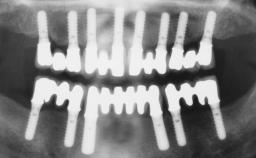

Immediate Loading of Six Implants in the Maxilla and Final Restoration with a Full-Arch CAD/CAM Zirconia FDP

A 63-year-old male patient was referred for a consultation and treatment of partial edentulism in the maxilla. The patient presented with residual anterior teeth and declined a partial removable prosthesis. He reported that the maxillary posterior teeth had been extracted due to mobility and periodontal disease two months before the consultation. The patient’s chief complaint was that his residual maxillary teeth were mobile and that he was unable to chew. The patient’s desire was a stable and comfortable fixed maxillary rehabilitation. The patient was a light smoker (fewer than 10 cigarettes/ day), and his medical history was without significant findings. He was not on any regular medication at the time of consultation. The extraoral examination revealed a normal physiognomy with a correct distribution of the facial thirds. The patient presented a low lip line, and the transition line between teeth and soft tissues was not exposed during a forced smile.